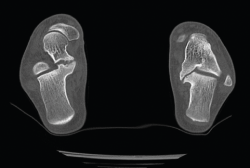

Figura 9. Pseudoartrosis subastragalina.

Caso 3. Pseudoartrosis subastragalina

Se trata de un caso del Dr. Cuervas-Mons, publicado en Techniques in Orthopedics(15), acerca de un paciente varón de 54 años que acude a la consulta con dolor del retropié y deformidad en varo. Tras la valoración, se evidencia pseudoartrosis sintomática (Figura 9), por lo que se decide llevar a cabo tratamiento quirúrgico.